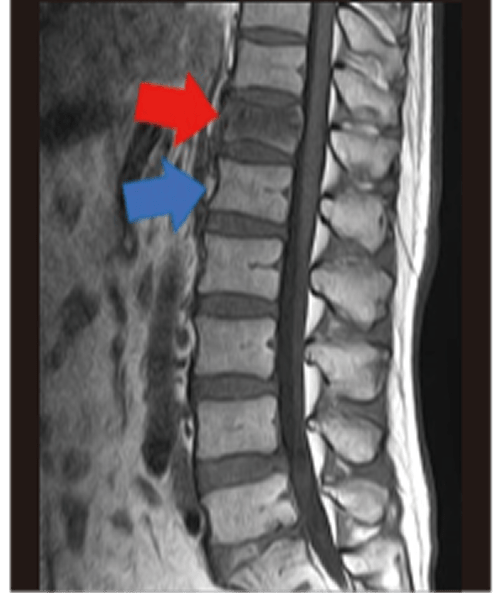

腰椎4番がやや前方(図向かって左側)へ向かって移動しています(青矢印)。

腰痛や坐骨神経痛などの原因となります。

椎体(背中や腰の骨)が骨折して通常より潰れてしまう状態です。

MRI画像で形が潰れてやや黒っぽくなっているのが確認できます(赤矢印が潰れた椎体で、青矢印が正常な椎体です)。

骨粗鬆(こつそしょう)症が原因で、本人の自覚なく骨折している場合もあります(いつの間にか骨折)。